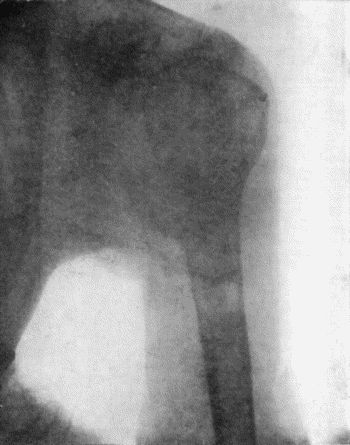

71.Radiogram of Aneurysm of Aorta 303

72.Sacculated Aneurysm of Abdominal Aorta 304